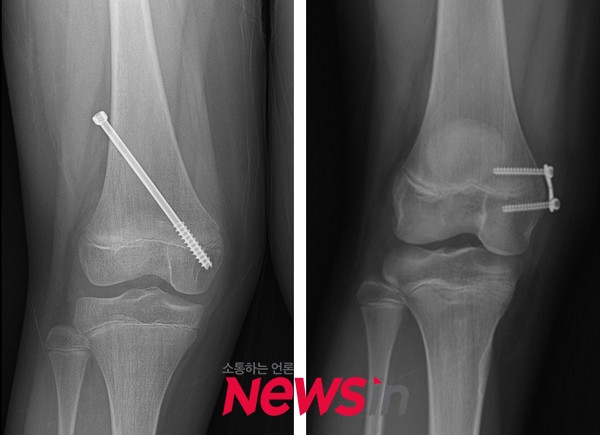

내반슬(오(O)자 다리)의 경우에는 성장판의 외측으로, 외반슬(엑스(X)자 다리)의 경우 성장판의 내측으로 금속을 위치시켜 부분적으로 성장판의 기능을 억제한다. 이를 위해 주로 나사못 또는 금속판이 이용된다. 이 수술을 시행 받은 소아 환자는 성장하면서 서서히 휜 다리가 교정되며 교정이 완료된 후 적용된 금속 기구를 제거하는 수술을 받게 된다.

연구팀은 외반슬 치료를 위해 성장판 부분 유합술을 시행 받은 소아 환자를 대상으로 하여 수술을 시행한 부위나 사용한 금속 기구에 따라 교정된 다리 변형이 어떻게 변화하는지 알아보기 위한 연구를 진행하였다.(수술 시 환자의 평균 나이는 11.2세였으며 교정이 완료될 때까지 평균 7개월이 소요되었다.) 나사못을 사용한 36례와 금속판을 사용한 37례를 성장 완료 후 비교 분석하였으며, 금속 제거 시점에서 성장 완료까지 3도 이상의 차이가 있는 경우 유의미한 변화가 있는 것으로 정의하였다.

그 결과 53%에서는 교정의 효과가 유지되었지만, 나머지에서는 교정 후 다리 모양이 유지되지 않고 재발 또는 과교정을 나타내었다. 성장판 기능의 억제를 위해 나사못을 사용하였을 때 금속판에 비해 짧은 교정 기간과 빠른 교정 속도를 보여주었다. 하지만 금속 제거 후에도 허벅지뼈에서 교정이 지속되어 과교정의 위험이 컸다. 반면에 금속판을 사용하였을 때는 허벅지뼈에서 변형이 재발되는 경향이 나타났다. 정강이뼈는 나사못과 금속판에 상관없이 제거 후에도 유의미한 변화를 보이지 않았다.